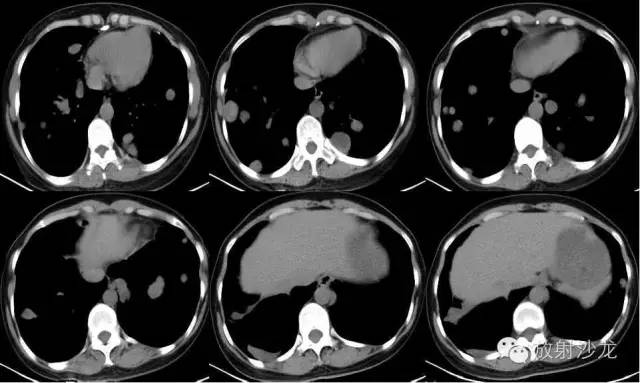

【影像表现】

双侧胸廓对称,纵隔居中。双肺可见散在多发大小不等类圆形软组织密度影,密度欠均,边界较清,最大者约5.32cm*7.88cm*6.75cm,右肺中叶、下叶可见一不规则形透亮影,内无肺纹理,纵隔未见明显肿大淋巴结,胸膜无增厚,右侧胸腔内可见弧形液体密度影。

【诊断结果】

双肺多发结节占位病变

右肺中下叶肺大泡

右侧胸腔积液